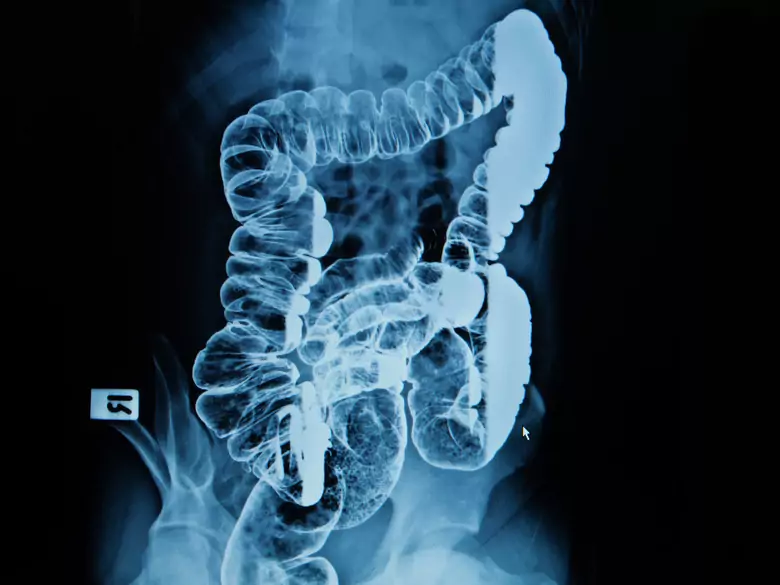

Żywienie drogą przewodu pokarmowego jest fizjologiczną metodą żywienia. Ten rodzaj odżywiania jest metodą z wyboru u chorych wymagających wsparcia żywieniowego, w momencie gdy całodzienna dieta nie jest w stanie pokryć zapotrzebowania energetycznego.